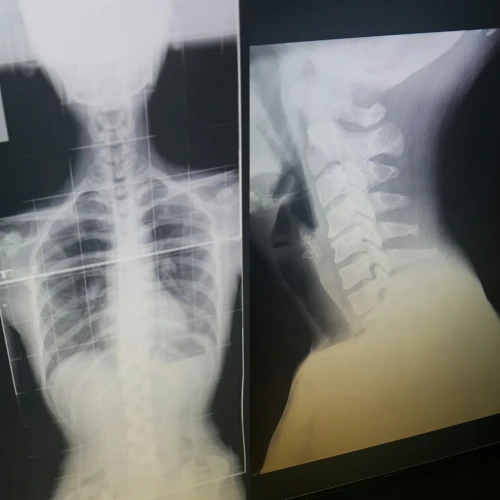

몇 년 전, 나는 목디스크 진단을 받았다.

그전부터 목을 뒤로 젖히는 것이 힘들었고 뻐근함은 일상처럼 느껴졌다.

피곤해서 그런가 보다, 별일 아니겠지 하며 대수롭지 않게 넘겼던 어느 날,

고개를 돌리는데 날카로운 통증이 온몸을 돌아다녔고 고개를 움직일 수 없었다.

어깨를 통째로 돌려야 겨우 시야가 따라왔다.

로봇처럼 뻣뻣한 몸을 이끌고 병원에 가니 의사는 의뢰서를 써주며 영상의학과에 가보라고 했다.

그때까지 일자목, 거북목, 경추 전만증, 후만증 같은 단어들은 들어본 적이 없었기에

'일자목'이라는 말을 듣고 큰일이라도 난 줄 알고 부랴부랴 다녀왔었다.

목이 부드럽게 돌아가고 불편함이 없으면 된다고 생각했는데 정상적인 목은 움직이는 것뿐만 아니라

C커브 형태로 충격을 흡수해 몸의 균형을 잡아주는 중요한 역할을 한다는 걸 그제야 알게 되었다.

<당시 사진> 인체는 정말 신기하다.